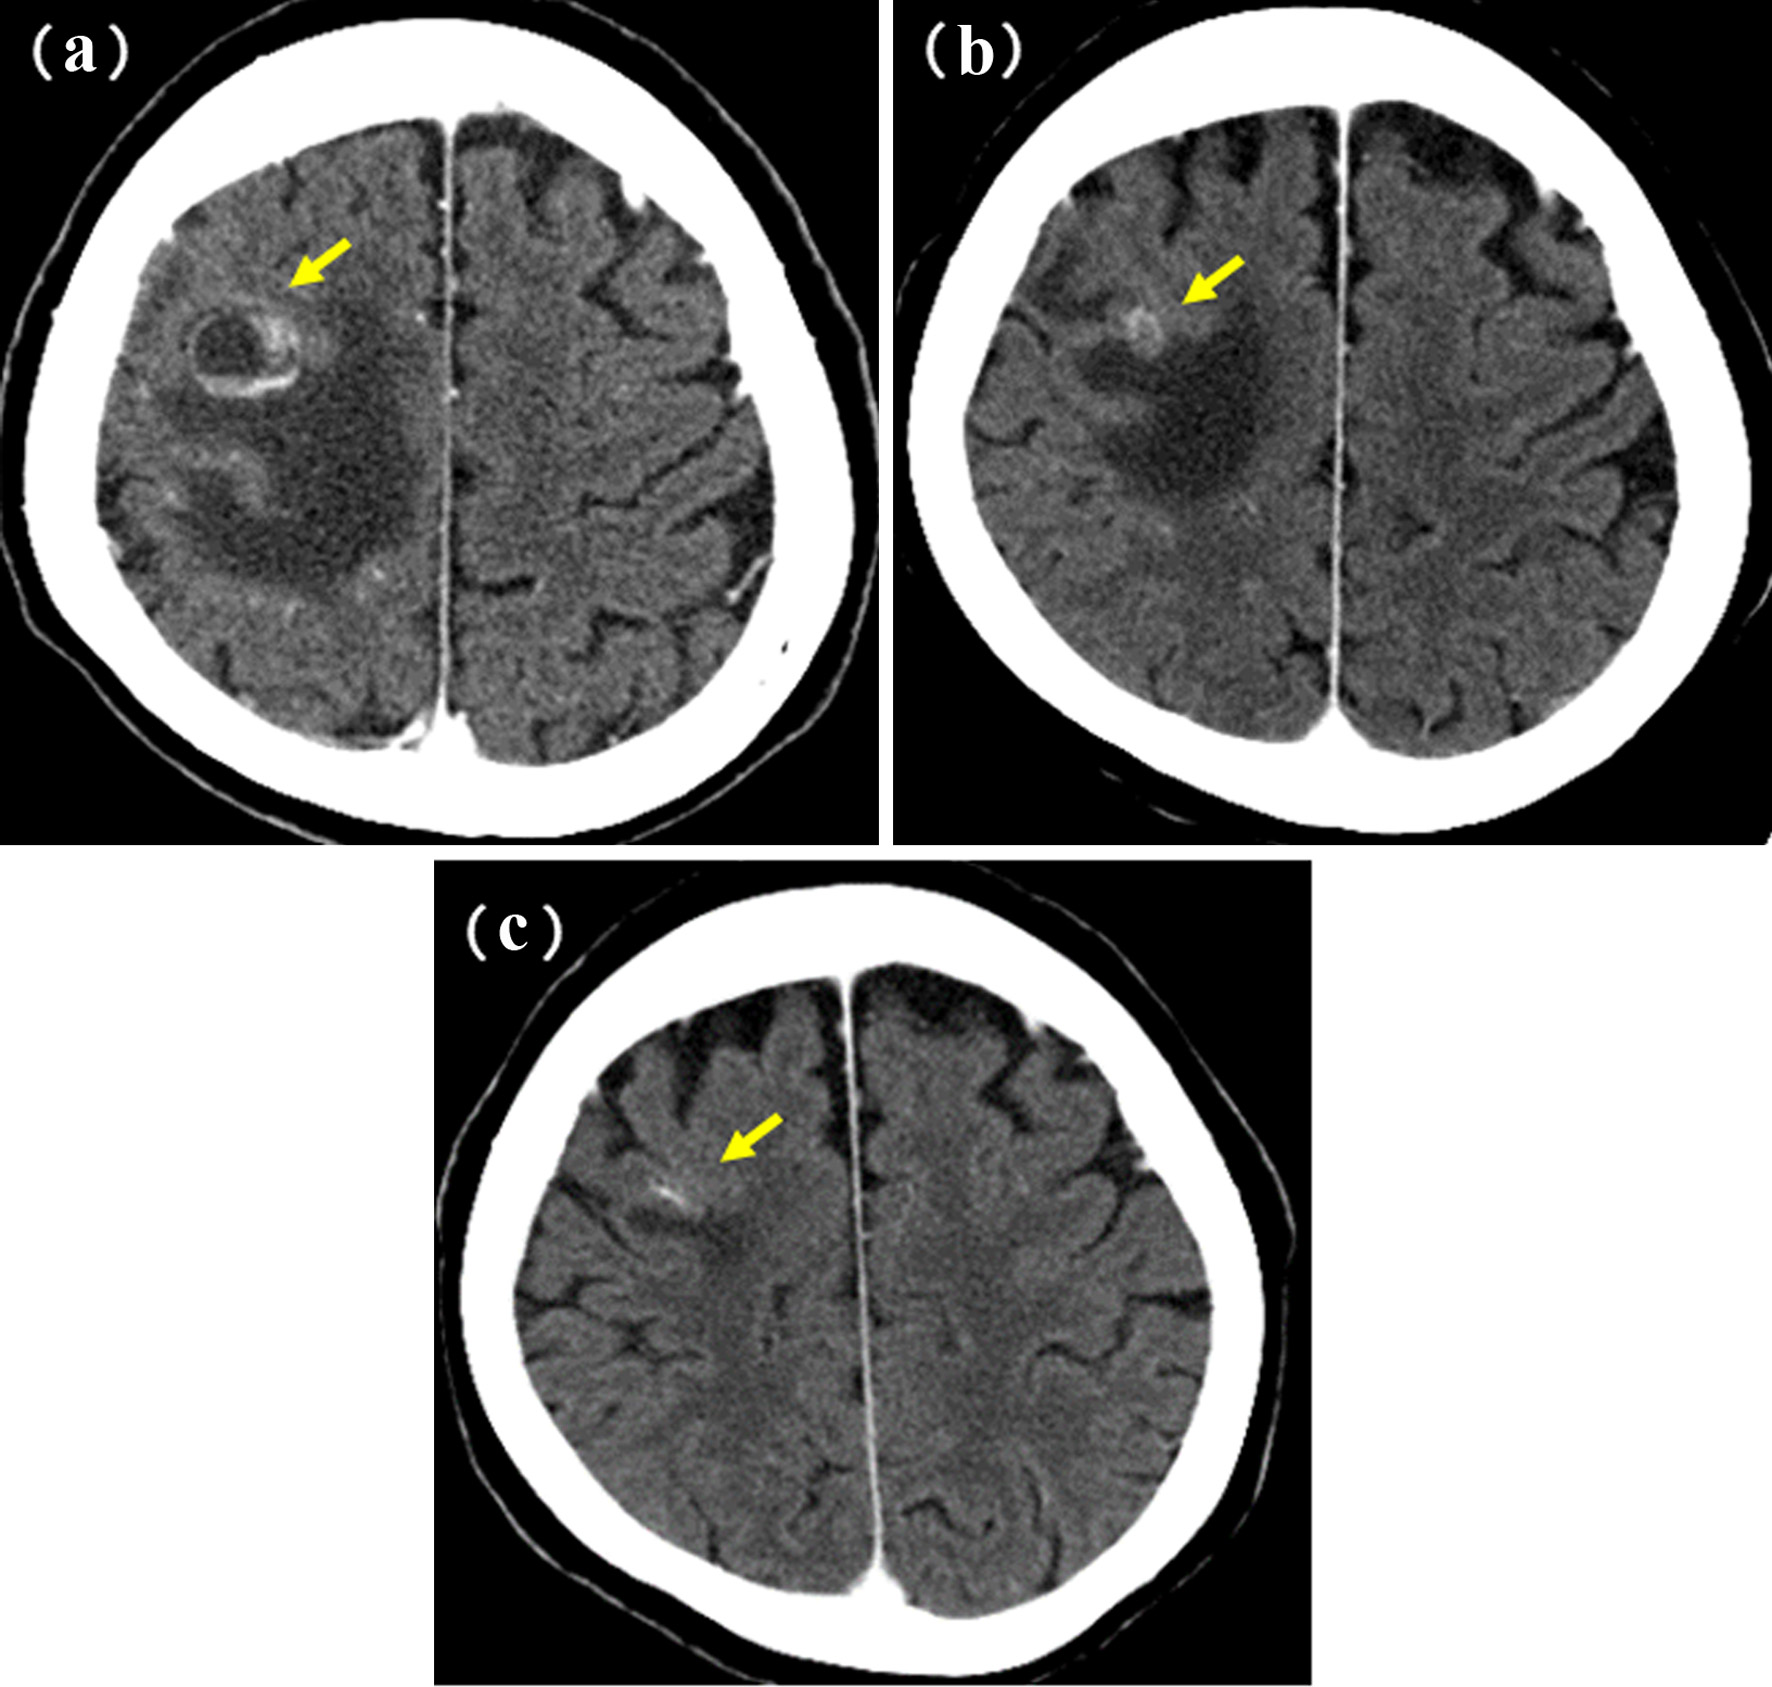

A 60-year-old woman was referred to our department because of a tumor shadow in the left middle lung field in November 2008. She had stopped smoking 5 years before, and was an ex-smoker with 30 pack-year smoking history. She had no significant medical history except for hyperlipidemia. Whole body computed tomography (CT) revealed a 29 × 27 mm sized tumor in the left S4 without distant metastasis. She was diagnosed as lung adenocarcinoma by bronchoscopy from left B4 (Fig. 4). She underwent left upper lobe resection and mediastinal lymph node dissection in December 2008. The pathological staging was p-stage IA (p-T1bN0M0). On genetic examination, no EGFR mutation was detected by PCR clamp method from the surgical specimen. In November 2010, 22 months after the surgery, she visited to our emergency room and presented paralyzed left hand. Brain CT with contrast enhancement revealed a 16 × 13 mm sized tumor with surrounding edema in the right frontal lobe (Fig. 5a). No other distant metastasis was found at that time. We suspected a solitary brain metastasis from lung cancer. She underwent gamma knife radiosurgery (GKR) at another hospital. In August 2011, 10 months after the first GKR, she again received the second GKR for the recurrence at the same brain metastatic site. Thereafter, despite of two courses of carboplatin (area under the curve (AUC) 6 mg/mL/min, day 1) and weekly paclitaxel (60 mg/m2, days 1, 8 and 15), the brain metastasis regrew (Fig. 5b). We started tri-weekly combination chemotherapy of pemetrexed (500 mg/m2, day 1) and intermittent erlotinib (150 mg, days 2 - 16) in November 2011 [9, 10], which reduced the brain metastasis (Fig. 5c). Pemetrexed was discontinued due to grade 3 of edema on the extremities in June 2013, after 28 courses. She continued 150 mg/day of erlotinib, and experienced neither progression nor severe adverse events in October 2022, 11 years after erlotinib initiation. After the initiation of pemetrexed and erlotinib, the Vysis Break Apart ALK fluorescence in situ hybridization (FISH) assay (by LSI Medience Corporation, Tokyo), approved by Japanese medical insurance in April 2012, detected ALK rearrangement in the surgical specimen.

![]() Click for large image | Figure 5. Brain metastasis of case 1. (a) Postoperative recurrence in November 2010. (b) Before (in October 2011) and (c) 1 year after (in October 2012) the initiation of pemetrexed and erlotinib. Yellow arrows show the brain metastases. |